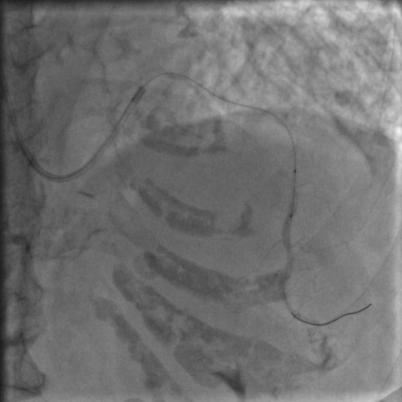

好像前降支的显影是比刚才多出来一小节,然而依然还没通,那拿个球囊扩一下吧,把刚才的球囊送到闭塞段,2、4、6个大气压,轻轻扩一下,再轻轻扩一下,好松开,再打点硝酸甘油,造影:

图10

额滴神呐,还不通,老婆婆一直在台上痛苦地*吟呻**,我们也很揪心。再打点欣维宁吧,86岁了不能打多,再给7ml,再送入血栓抽吸导管,抽吸,依然可以看到注射器里面抽出来好多血栓,好,造影:

救命,我们已经快要绝望了,刚刚好不容易搞出来的那一小段,现在又堵上了。本来以为是个简单的病变,血栓怎么这么顽固。再来一次血栓抽吸,抽吸导管尽量往下送,造影: